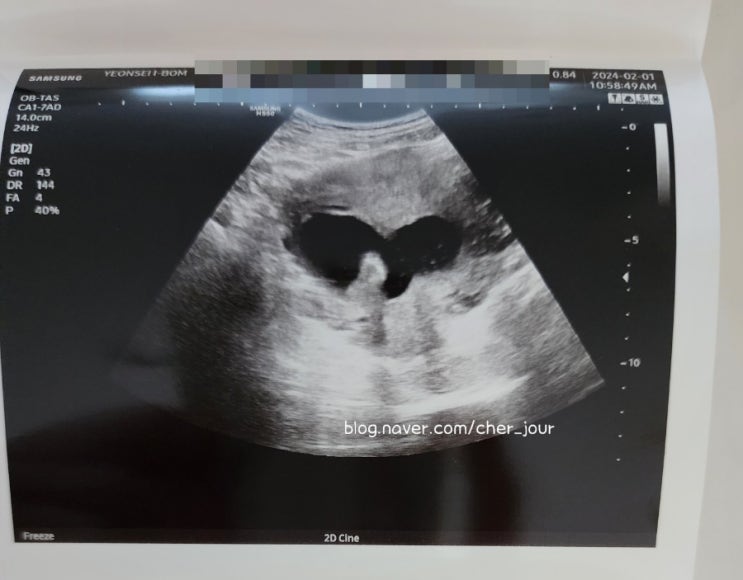

[시험관 아기] 어느덧 임신 18주 19주 / 임신 18주 몸무게 / 임산부 철분제 / 임산부 영양제 / 임산부 오메가3

#임신18주몸무게 #임신19주 #임산부영양제 #임산부철분제 #임산부오메가3 어느덧 임신 19주 어느덧 임신 19...

[시험관아기] 임신 7주 / 임신 8주 / 시험관 비용 / 면역글로블린주사 / 인트라리피드

#시험관비용 #면역글로블린 #인트라리피트 건강하게 잘자라는 중 7주가 되어 드디어 태아 심장소리를 들었...